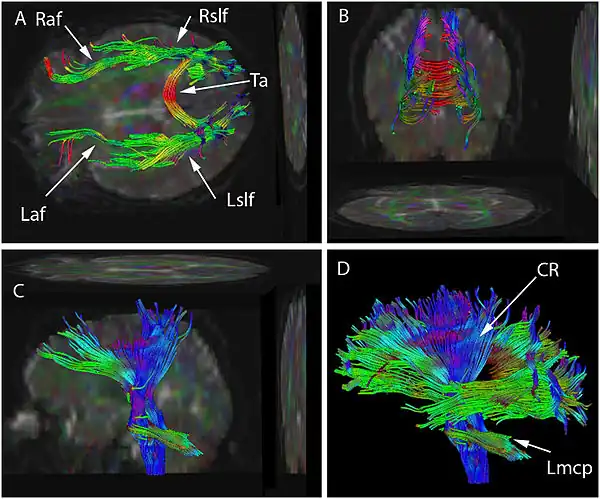

On voit ici les vues supérieures (A), postérieures (B) et latérales (C et D).

La tractographie est réalisée grâce à l'imagerie du tenseur de diffusion. L'IRM de diffusion, introduite, notamment pour son potentiel en neuroimagerie par Denis Le Bihan dès 1985 [1],[2] permet d'obtenir des images de la diffusion moléculaire, notamment de l'eau. Une évolution de l'IRM de diffusion, l'imagerie du Tenseur de Diffusion [3],[4], permet de caractériser la diffusion moléculaire dans les 3 dimensions de l'espace. La diffusion libre se produit de manière homogène dans toutes les directions (mouvement brownien). On l'appelle diffusion isotropique. Si l'eau diffuse dans un milieu avec des barrières, la diffusion sera privilégiée dans certaines directions. On l'appelle diffusion anisotropique. Dans un tel cas, la mobilité des molécules à partir de leur origine de départ a une forme différente d'une sphère. La forme peut-être ellipsoïde. Cette technique est appelée technique d'imagerie du tenseur de diffusion. Les barrières peuvent être de multiples types : membranes cellulaires, axones, gaines de myéline, etc. Dans le cerveau, la principale barrière est la gaine de myéline. Des faisceaux d'axones forment une barrière empêchant une diffusion perpendiculaire et un chemin pour la diffusion parallèle le long de l'orientation des fibres. On s'attend à ce que la diffusion anisotropique soit augmentée dans les zones d'ordre axonal maximum. Dans certaines pathologies, la structure des axones est perturbée comme dans les traumatismes, les tumeurs ou les inflammations. L'anisotropie, par destruction ou désorganisation des barrières est donc augmentée. L'anisotropie est mesurée de différentes manières. L'une d'entre elles consiste à évaluer un ratio appelé anisotropie fractionnelle (AF). Une anisotropie de 0 correspond à une sphère parfaite alors qu'un ratio à 1 correspond à une diffusion linéaire idéale. Des trajets bien délimitables ont une AF plus grande que 0,20. Peu de régions ont une AF de plus de 0,80. La valeur donne une information sur la non-sphéricité de la diffusion mais ne donne pas d'information sur sa direction. Chaque anisotropie est liée à une orientation sur un axe prédominant (direction prédominate de la diffusion) Des programmes informatiques sont capables d'extraire cette information directionnelle. Cette information additionnelle est difficile à représenter sur des images en 2D en échelles de gris. Pour surmonter ce problème, un code coloré est ajouté. Des couleurs basiques informent sur l'orientation des fibres dans un système avec des coordonnées dans les 3 dimensions. On parle de plan anisotropique. Conventions de couleurs :

- Le rouge indique une direction sur l'axe de X: droite à gauche ou gauche à droite.

- Le vert indique des directions selon l'axe des Y : postérieur vers antérieur ou antérieur vers postérieur.

- Le bleu indique des directions sur l'axe des Z : des pieds à la tête ou de la tête aux pieds.